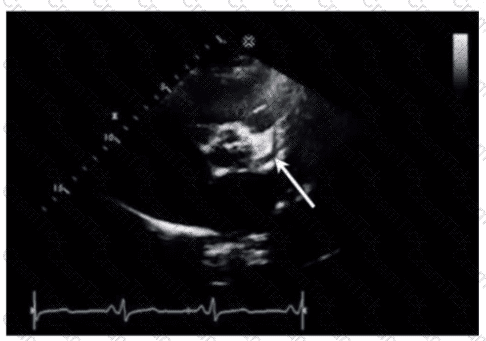

Which left ventricular regional wall segment is indicated by the arrow on this image?